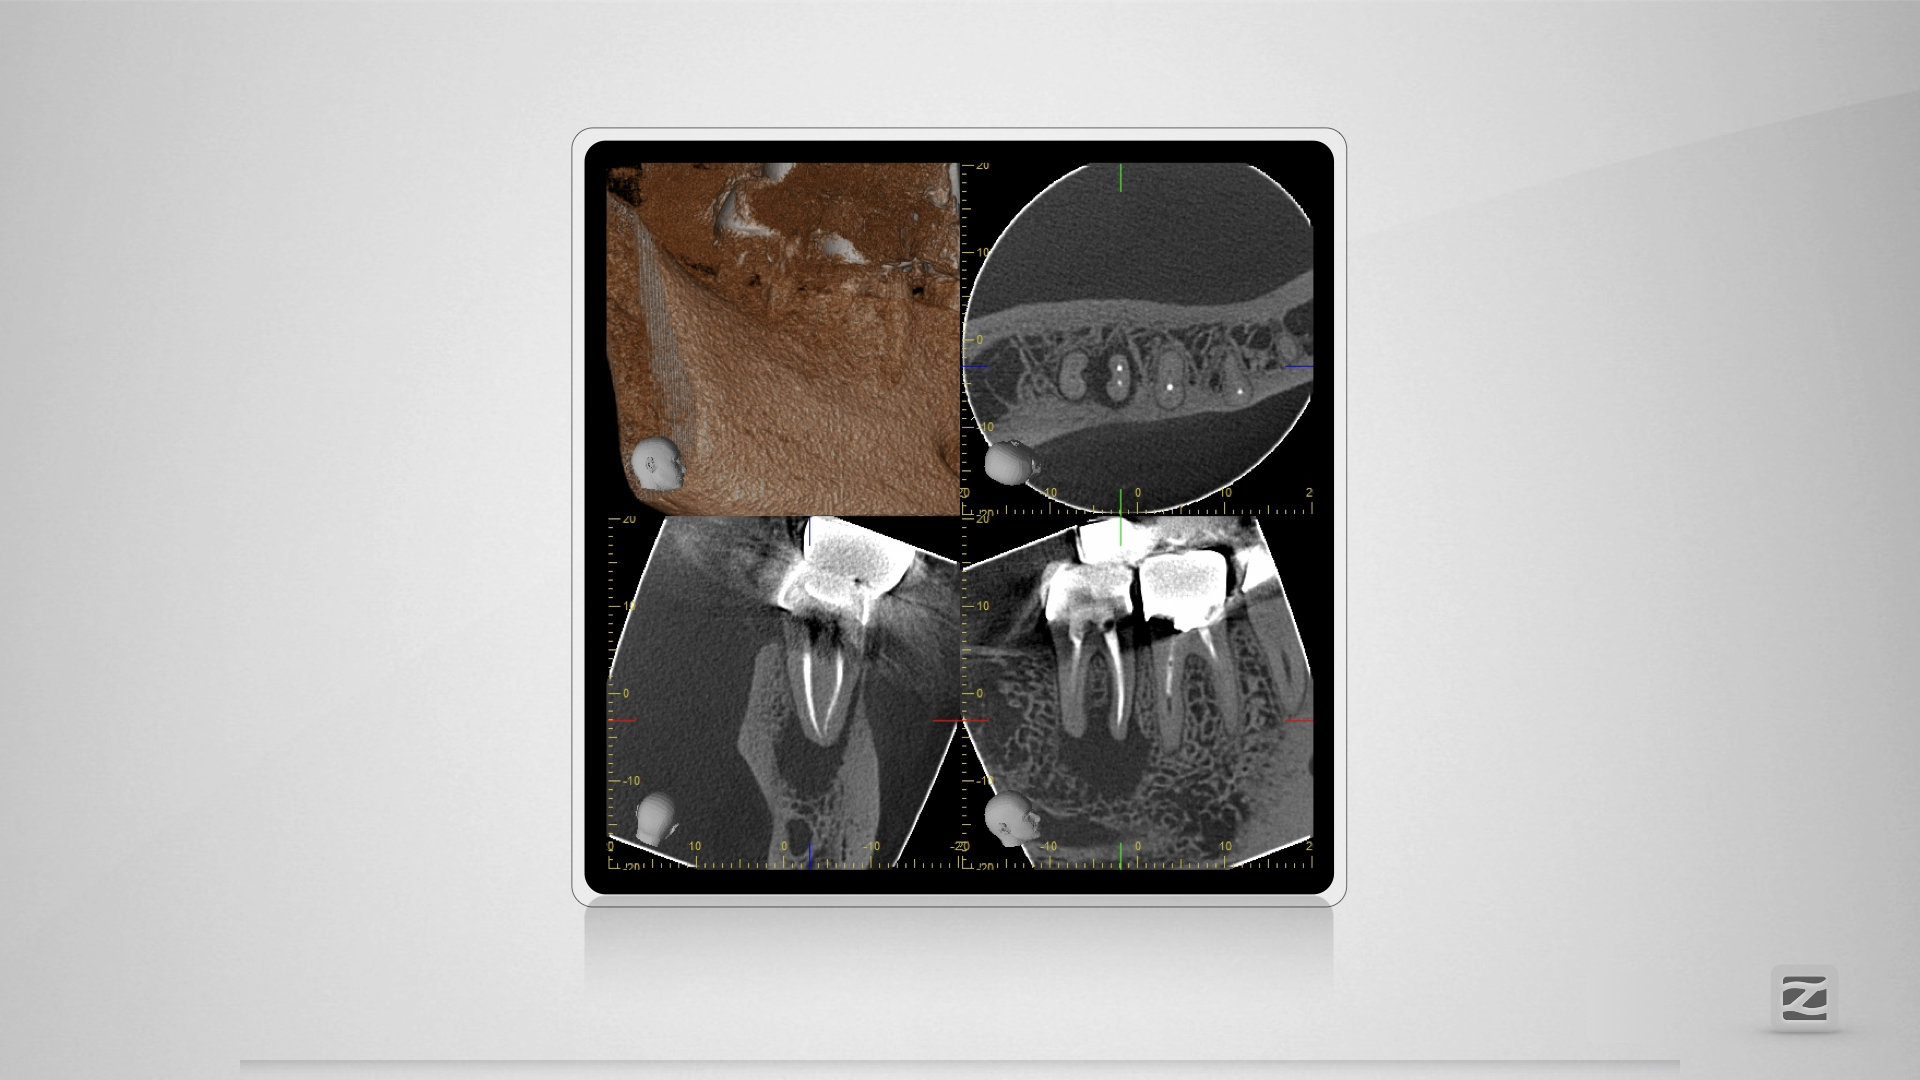

47D.002

Kuhfuß